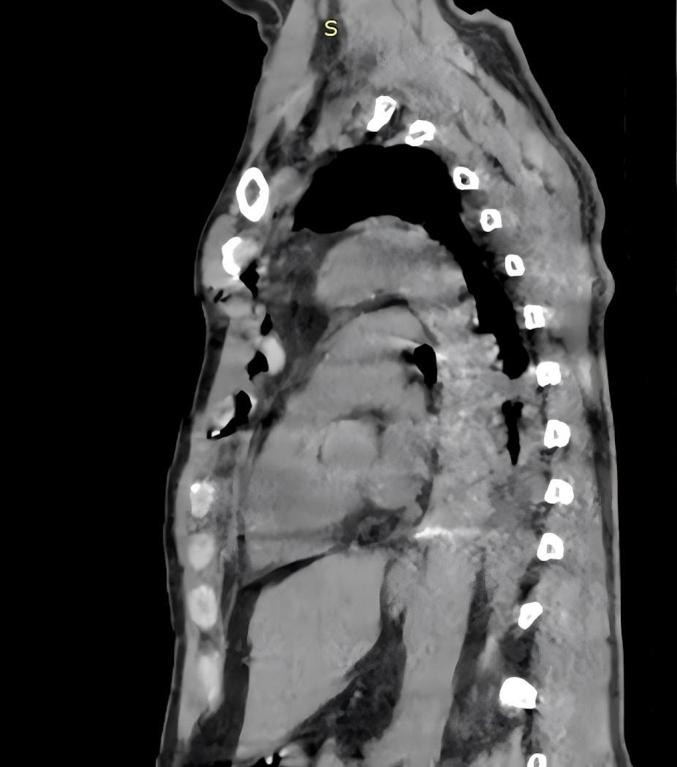

A 53-year-old male patient with sternal manubrium avulsion fracture and costal cartilage fractures caused by a bull goring injury was treated with a multi-material combined fixation strategy (wire cerclage reduction + titanium plate and screw fixation + memory alloy embracing device). The wire threading technique and flexible costal cartilage fixation technique were optimized during the surgery.

The surgery successfully achieved stable fixation of the sternum and costal cartilage, with postoperative CT showing good alignment and disappearance of paradoxical breathing. The patient did not undergo any loosening of the internal fixation, recovering smoothly.

The combined application of wire cerclage, plate fixation, and memory alloy internal fixation can effectively treat sternal manubrium avulsion fractures combined with flail chest.

方法

结果

结论